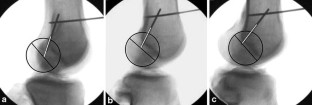

Correct placement of the tibial and femoral bone tunnel is prerequisite to a successful anterior cruciate ligament (ACL) reconstruction. This study compares the resulting radiographic femoral bone tunnel position of two commonly used techniques for arthroscopically assisted drilling of the femoral bone tunnel: the transtibial approach or drilling through the anteromedial arthroscopy portal. The resulting bone tunnel position was assessed in postoperative knee radiographs of 70 patients after ACL reconstruction. Three independent observers identified the femoral bone tunnel and determined its position in the lateral and A–P view. Differences in femoral tunnel position between transtibial and anteromedial drilling were evaluated. In the sagittal plane, significantly more femoral bone tunnels were positioned close to the reference value using an anteromedial drilling technique (86%) when compared to transtibial drilling (57%). Drilling through the transtibial tunnel resulted in a significantly more anterior position of the femoral tunnel. In the frontal plane, femoral bone tunnels which were placed through the anteromedial arthroscopy portal displayed a significantly greater angulation towards the lateral condylar cortex (50.92°) when compared to transtibial drilling (58.82°). In conclusion, drilling the femoral tunnel through the anteromedial arthroscopy portal results in a radiographic femoral bone tunnel position which is suggested to allow stabilization of both anterior tibial translation and rotational instability when using a single bundle reconstruction technique. Further studies may evaluate if there are any clinical advantages using the anteromedial portal technique.

Fig. 1